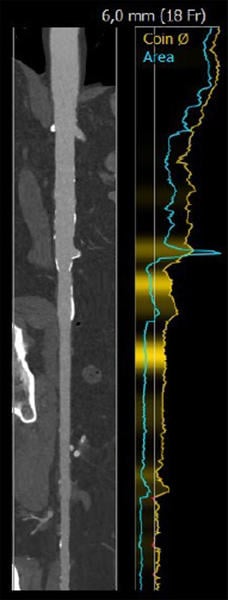

Case planning: CT

LAO 3° - cranial 19°

RAO 14° - caudal 9°